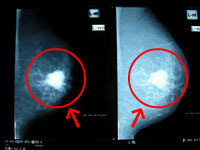

マンモグラフィーは、乳房にエックス線を当てる検査で、がんの疑いがある微細な石灰化物も検出できるため、乳がんの早期発見に大きく寄与します。レントゲンと同じ原理で、石灰化物は白く写ります。ただし、乳腺が発達している10~30代の場合、乳腺が白く写りこんでしまうため、判別がしにくくなる場合があります。